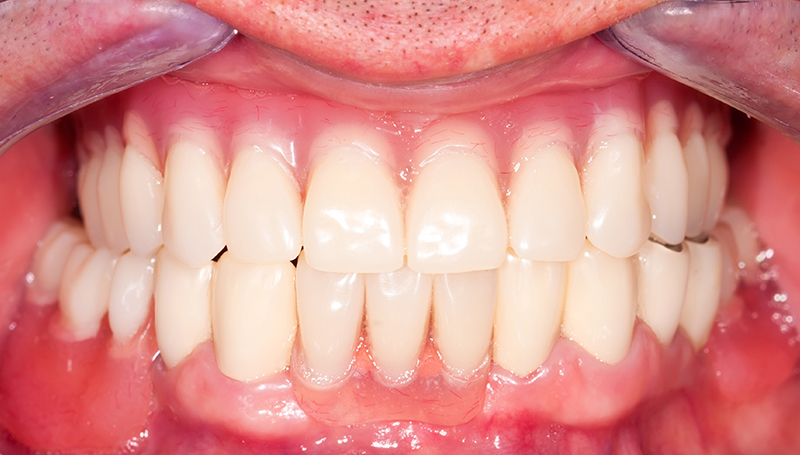

Сразу после операции изготовленный протез фиксируется к имплантам на винты. По завершению операции, можно сразу давать нагрузку на протез. Теперь вы можете есть, говорить и улыбаться совершенно ничего не стесняясь.

Установка протеза

Результаты лечения

Вы получите естественную и привлекательную улыбку

Наши работы

Верните радость улыбки

и уверенность в себе